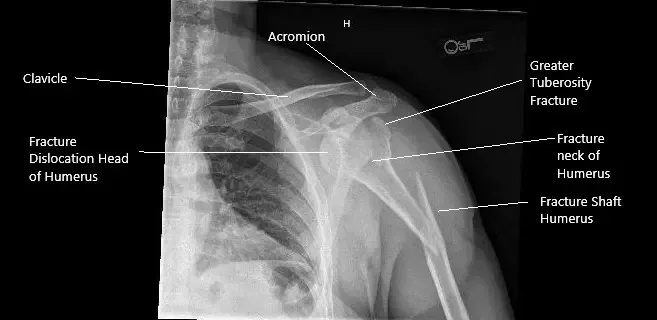

Radiografía preoperatoria del hombro izquierdo en vista AP.

La radiografía reveló una fractura en espiral del eje proximal del húmero con angulación dorsal en el lugar de la fractura. Hubo una fractura del cuello quirúrgico del húmero con una fractura de mayor tuberosidad. Una tomografía computarizada del hombro izquierdo reveló una fractura conminuta de la cabeza del húmero izquierdo con luxación antero-inferior del fragmento principal de fractura, incluida la cabeza del húmer.

Un gran fragmento conminuto permanece en las inmediaciones de la glenoide. Se observa un pequeño fragmento lineal entre la cabeza húmeral y la escápula izquierda. Existe un componente principal de fractura separada en la diáfisis humeral proximal con angulación inferior.